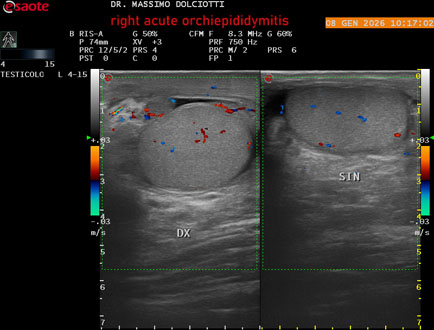

Data inserimento: 08/01/2026

Ecografia del: 08/01/2026

Strumento: Esaote MyLab Eight

Sonda: Lineare Multifrequenza 4-15 MHz

Età Paziente: M 74 anni

Motivazione dell'esame: da 3 giorni dolore e tumefazione al testicolo destro.

Commento all'esame: le immagini ed il video documentano il didimo destro, aumentato di volume, con incremento della vascolarizzazione; aumentato di volume e di vascolarizzazione anche l'epididimo destro, Normale il didimo sin e l'epididimo sinistro, Gli elementi ecografici segnalati orientano per orchiepididimite destra acuta.

Conclusioni: orchiepididimite destra acuta (right acute orchiepididymitis).

Presentazione: Dr. Massimo Dolciotti - Ancona